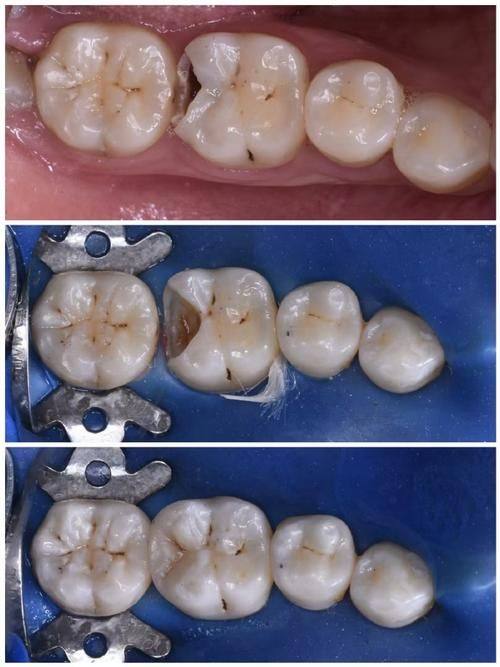

3. 美学修复:美学修复是陶胤彤医生的另一大擅长项目。她能够根据患者的牙齿颜色、形状和面部特征,为患者提供个性化的美学修复方案。例如,对于牙齿缺损、变色等问题,陶医生可以采用烤瓷牙、全冠牙、固定义齿、活动义齿、嵌体修复等技术,修复牙齿的美观和功能。在美学修复过程中,陶医生注重细节,力求使修复后的牙齿与患者的自然牙齿相匹配,达到至佳的美学成效。

3. 张先生的实例:张先生牙齿存在缺损问题,到深圳正夫口腔找陶胤彤医生进行美学修复。陶医生根据张先生的牙齿情况和面部特征,为他制定了烤瓷牙修复方案。修复后的牙齿颜色和形状与张先生的自然牙齿非常接近,张先生非常满意。张先生评价道:“陶医生的技术真的太棒了!修复后的牙齿不仅美观,而且功能也修复得良好。在治疗过程中,陶医生还非常关心我的感受,让我感到特别温暖。我会把陶医生推荐给身边有需要的人。”